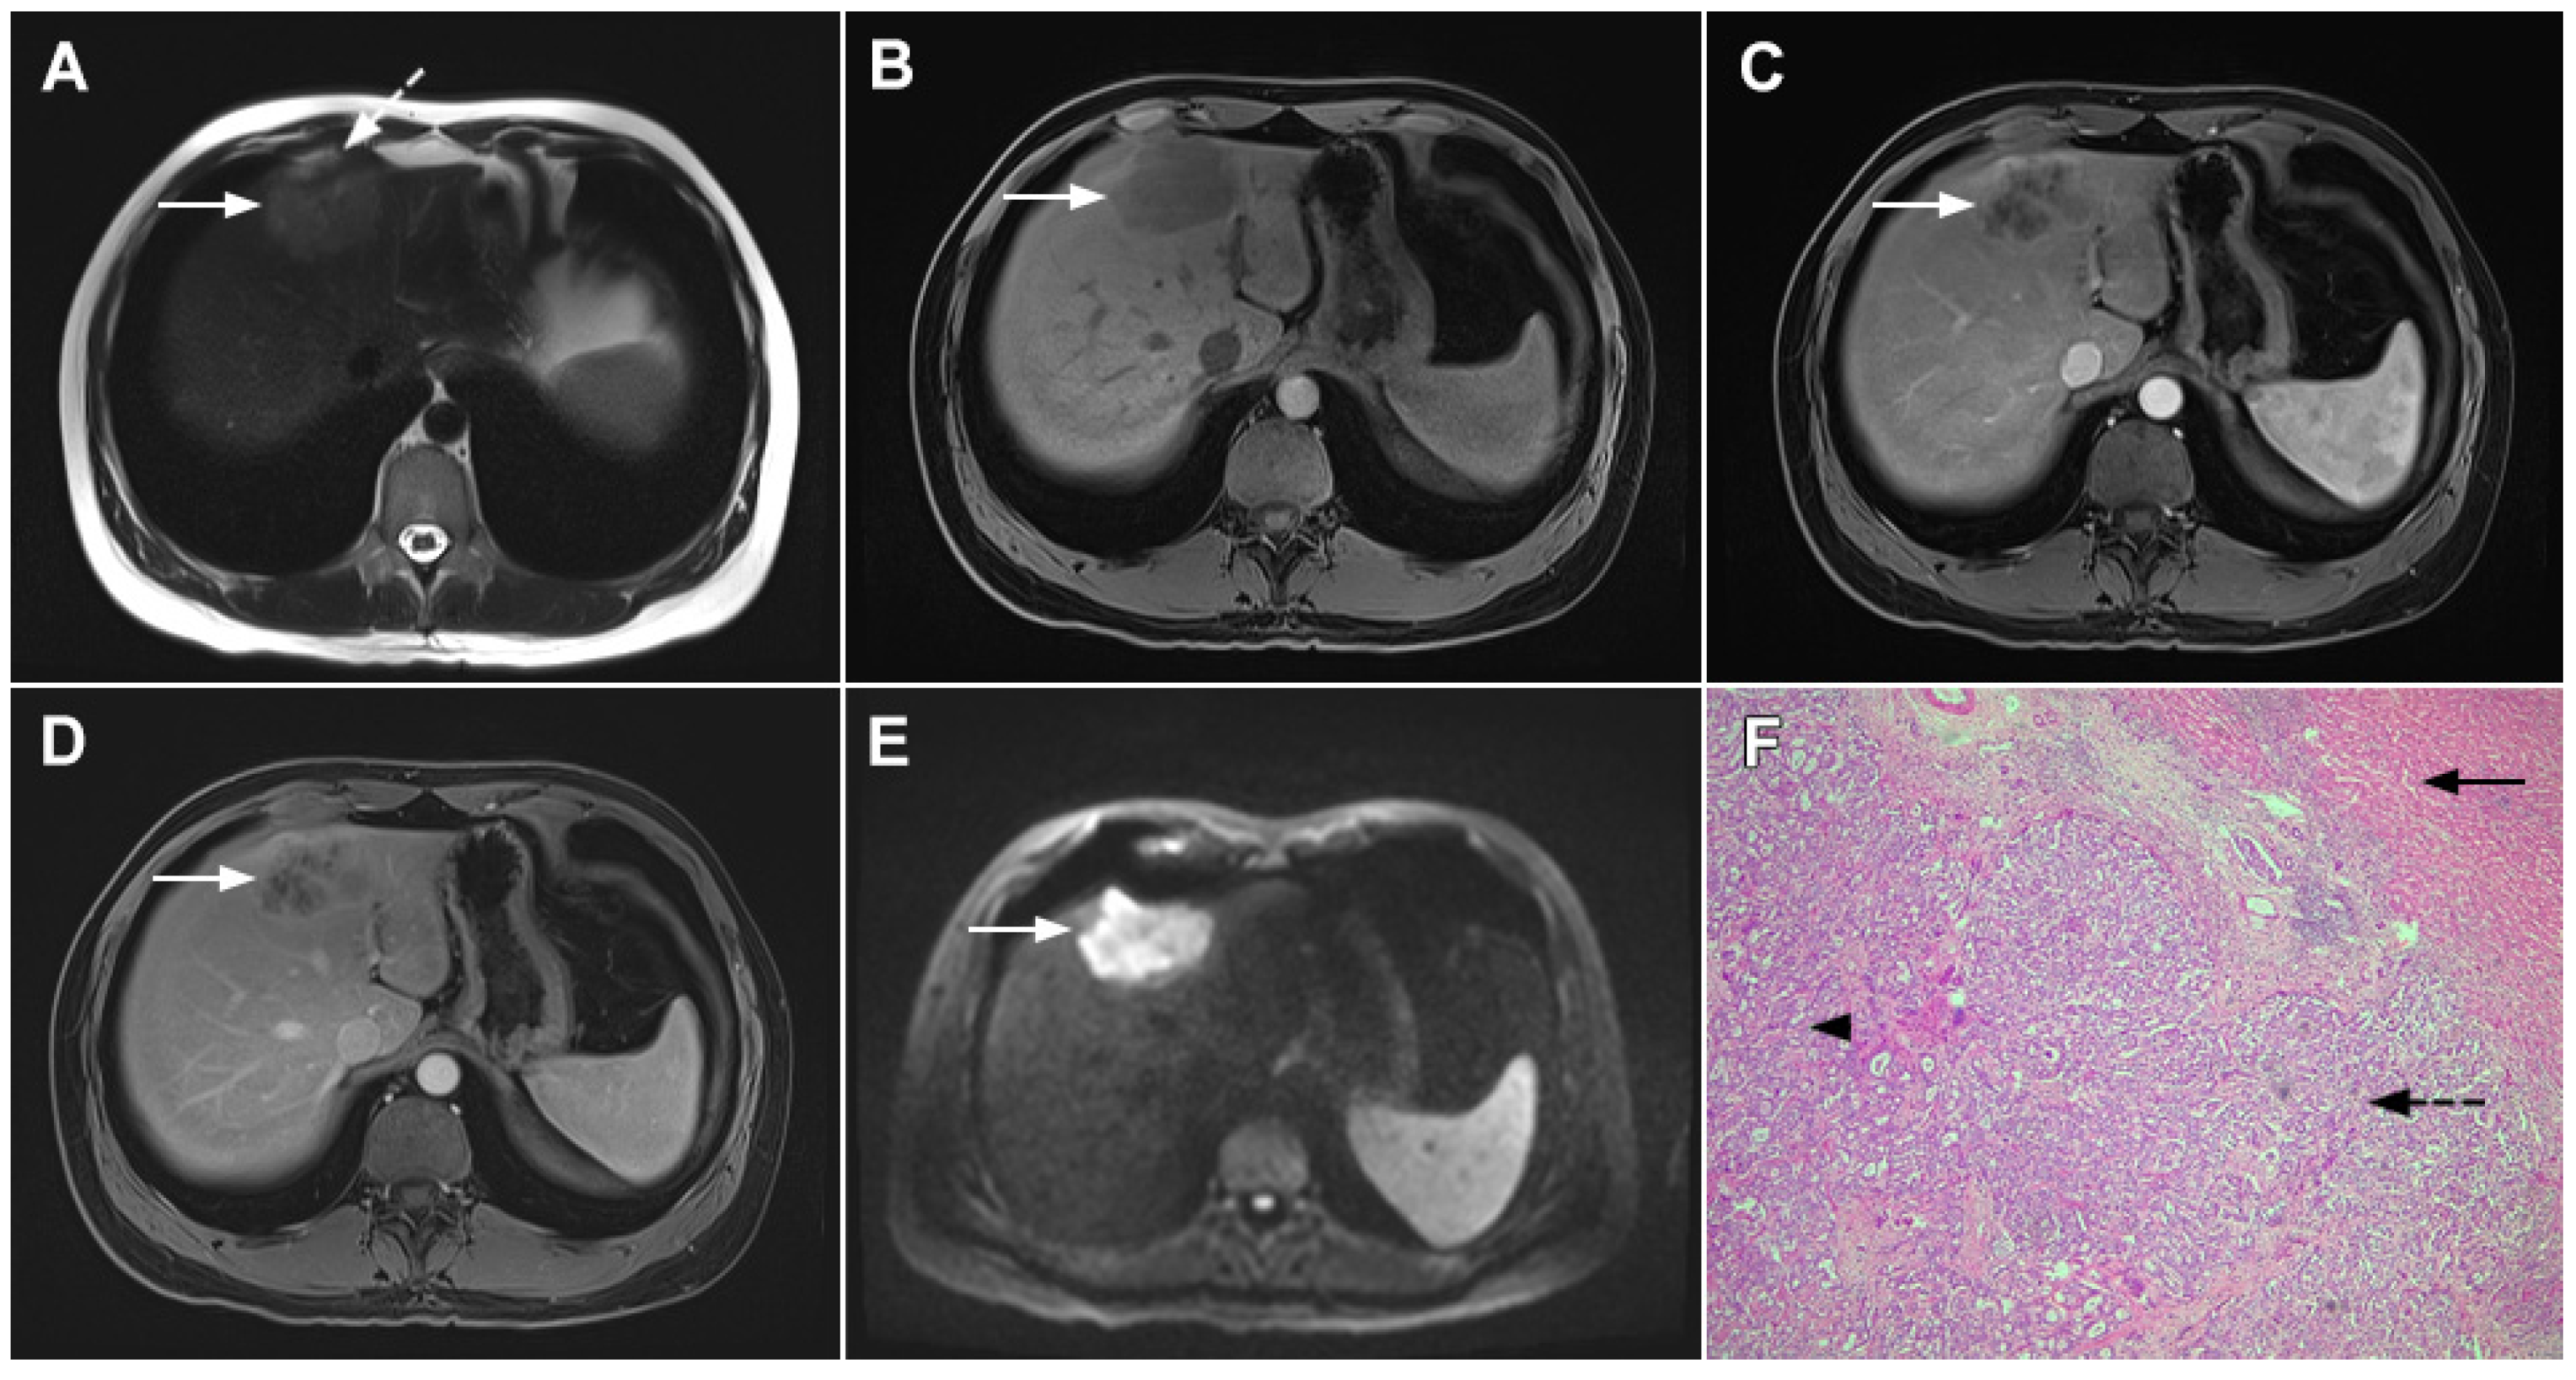

3.1.2. Sclerosing Hemangioma

3.1.3. Inflammatory Pseudotumor